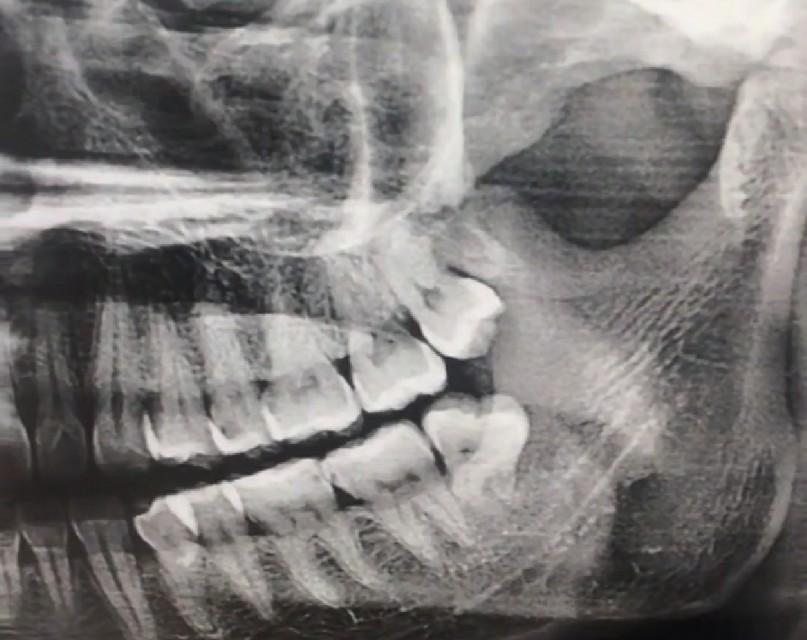

下顎的智齒拔起來(lái)可以說(shuō)相當(dāng)?shù)睦щy,它有逆生長(zhǎng)的、壓根不露頭的、還有牙根帶鉤的、關(guān)鍵是下顎接近腦神經(jīng),拔下額的智齒必須要拍牙齒圖片,拍一個(gè)圖片也就50塊錢左右,如果圖片出來(lái)智齒的位置比較麻煩,好還是多花點(diǎn)錢去三甲醫(yī)院拔除,下顎智齒拔除的困難度不同價(jià)格也不同,有的隱藏智齒需要開刀縫合切割,長(zhǎng)時(shí)間甚至需要醫(yī)生一個(gè)多小時(shí)的折騰,三甲醫(yī)院的價(jià)格從800到2000也就不奇怪了。